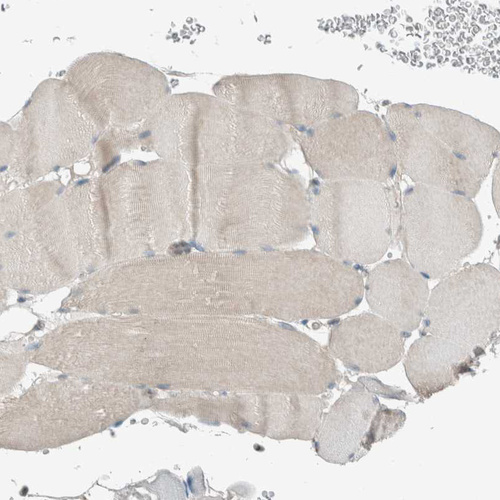

Immunohistochemical staining of human placenta shows moderate cytoplasmic positivity in trophoblastic cells.